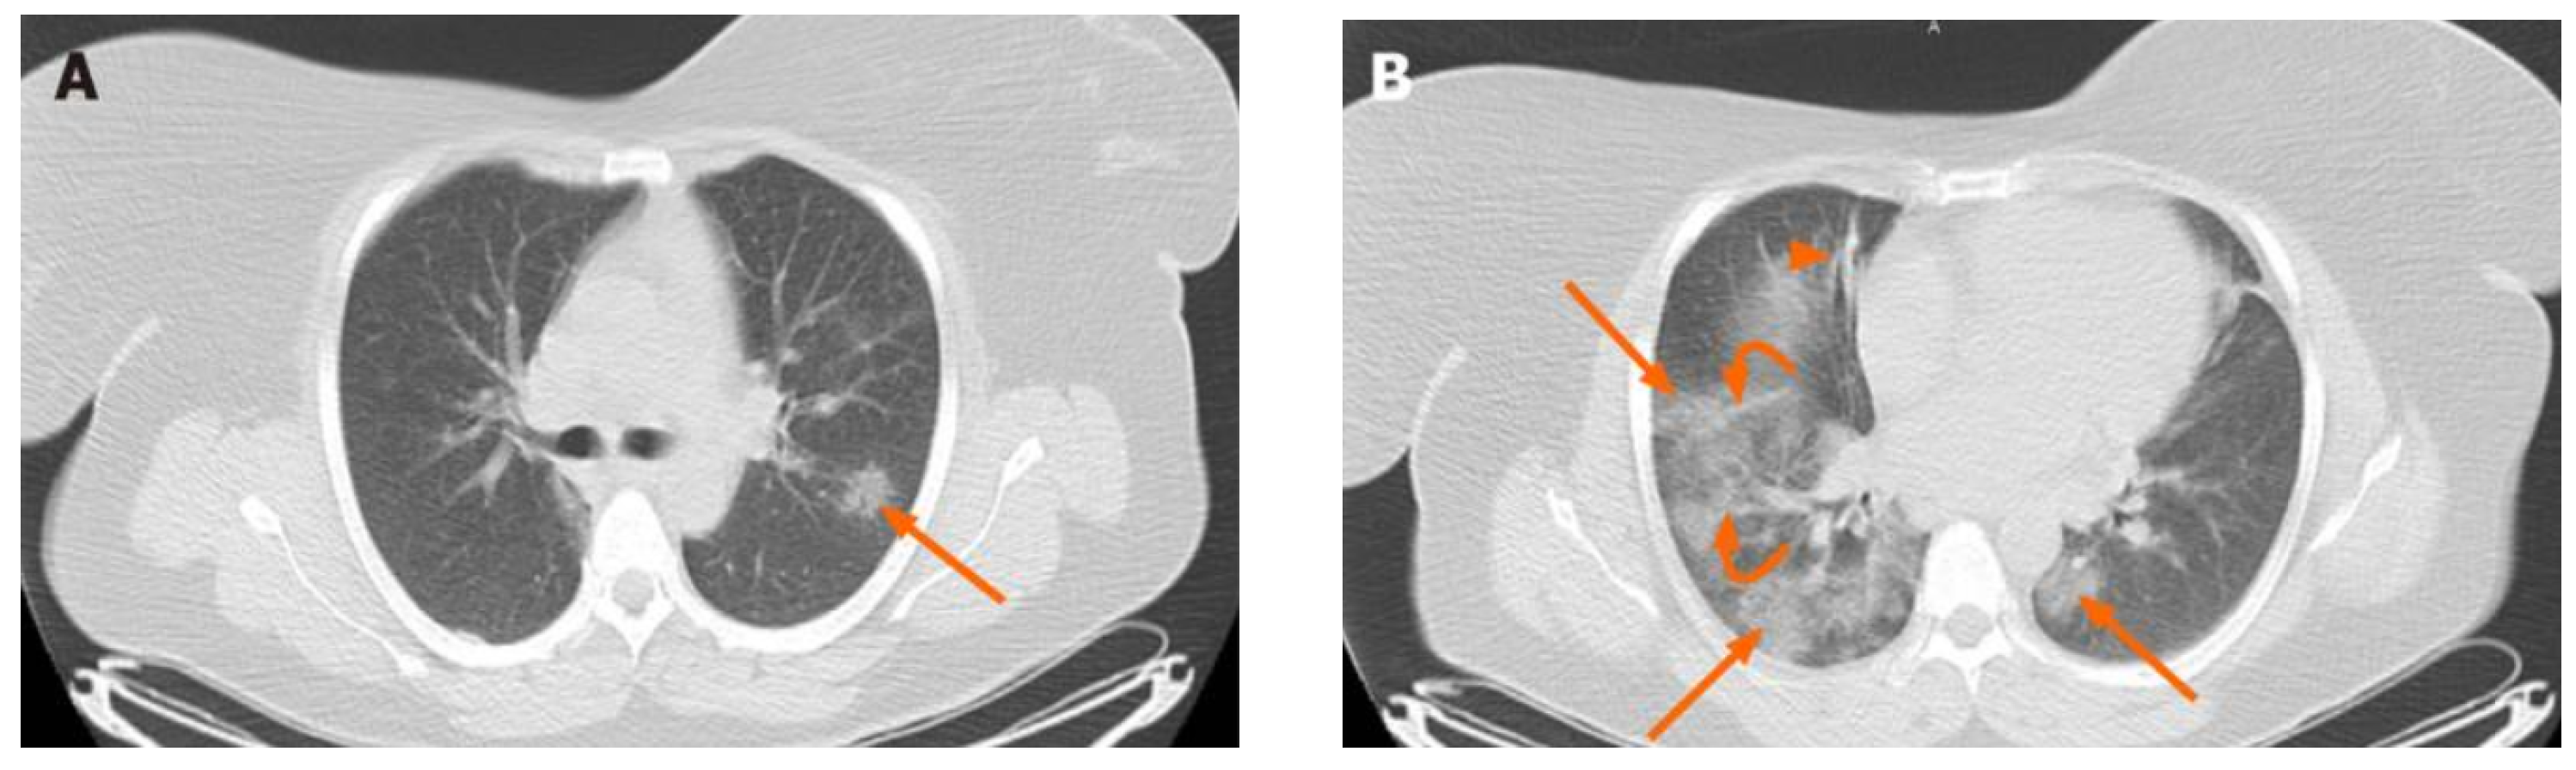

From a strictly medical perspective, the idea of the seriousness of the patient’s condition is emphasized once the patient comes into contact with the current illness. More specifically, the main CT features are bilateral multifocal ground-glass pulmonary opacities overlapping consolidation, bronchiolar wall thickening, rounded opacities, and interlobular septal thickening [8]. In a specific case (Figure 1), the axial-computed tomography of the chest shows bilateral multifocal ground-glass opacities represented by red arrows, peribronchial interstitial thickening (arrow B), and reticular opacities (curved arrows; B). Pulmonary opacities with ground-glass appearance are most common and are mainly seen as bilateral and multifocal opacities with peripheral and posterior distribution. Pure consolidations are less common and may be seen later in the course of the disease or at older ages.

Figure 1.

Chest radiographsof a 46-year-old female patient with fever and dry cough [9]. Axial chest computed tomography shows bilateral multifocal ground glass opacities (arrows; (A,B)), peribronchial interstitial thickening (arrowhead; (B)) and reticular opacities (curved arrows; (B)), consistent with coronavirus disease 2019 pneumonia.